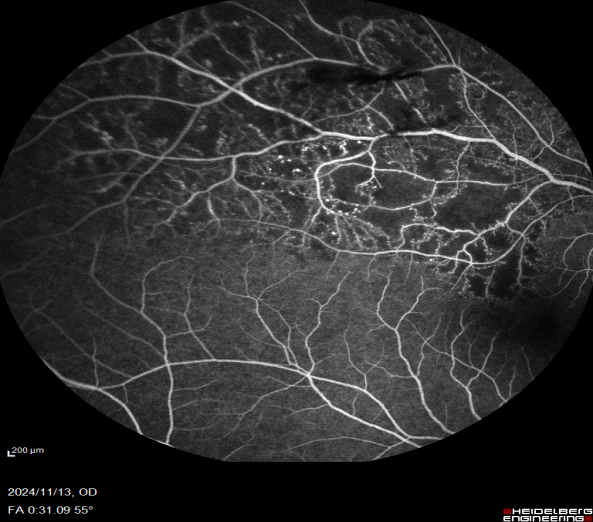

近年来,随着高血压、糖尿病、高血脂等患者的增多,这些疾病导致的视网膜静脉阻塞、糖尿病视网膜病变、黄斑水肿等眼底并发症的发病率有逐年增高的趋势。我院眼科在临床治疗工作中,发现患有眼底疾病的患者明显增多,而这些眼底疾病需要早筛查、早发现、早治疗,如果等到晚期出现视网膜脱离等严重并发症,等待患者的将是永久的失明。

视网膜激光光凝术是治疗眼底疾病的主要方法。利用激光的热效应,作用于眼底的病变部位,使之被光凝破坏形成瘢痕,从而达到封闭或破坏缺氧区的治疗技术,可以有效地控制视网膜细胞的代谢,减少视网膜水肿渗出、减轻黄斑水肿、改善视网膜供氧、抑制新生血管形成,阻止视网膜病变的进展,防止视网膜遭到进一步的损害。

常用于糖尿病视网膜病变、视网膜静脉阻塞、视网膜血管炎、视网膜血管瘤、中心性浆液性脉络膜视网膜病变、外层渗出性视网膜病变、家族性渗出性视网膜病变、早产儿视网膜病变、视网膜裂孔、视网膜变性等。